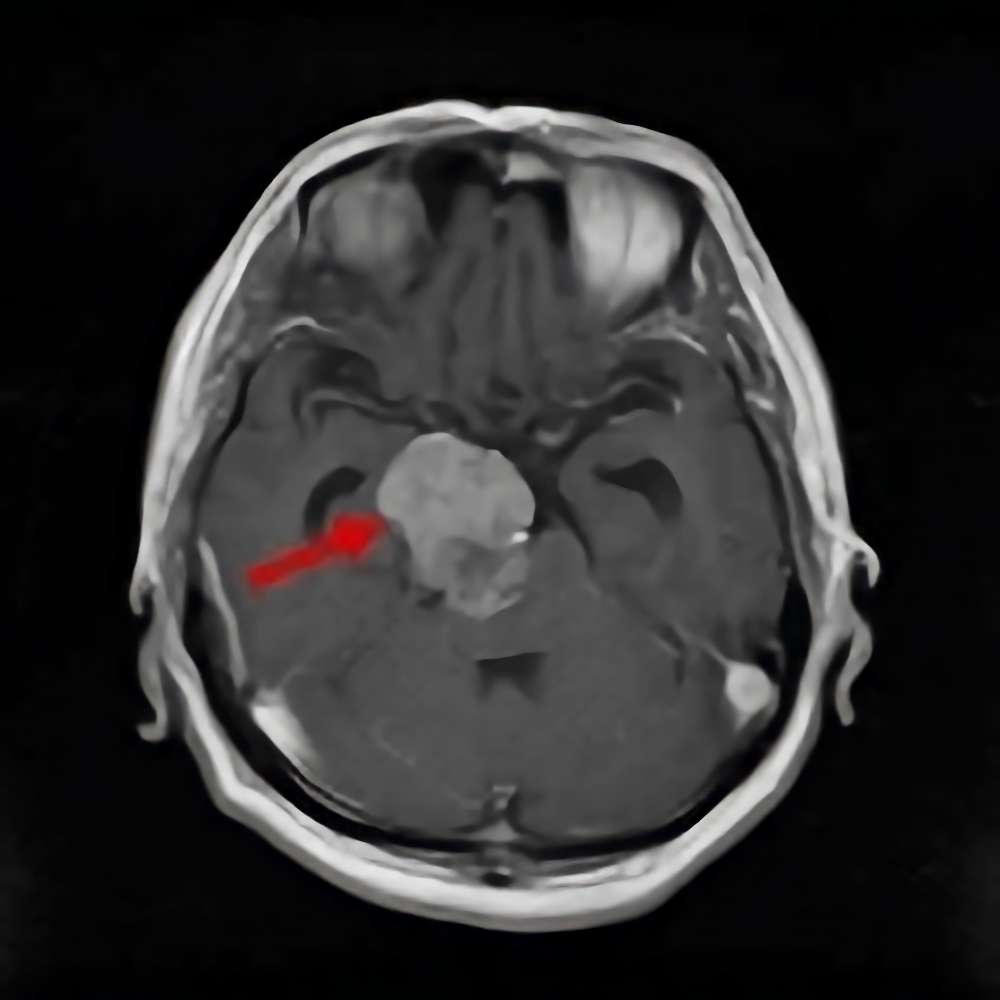

'14年6月

40代

海綿状血管腫

No.’14_104 手術前1

No.’14_104 摘出 前

No.’14_104 摘出 後